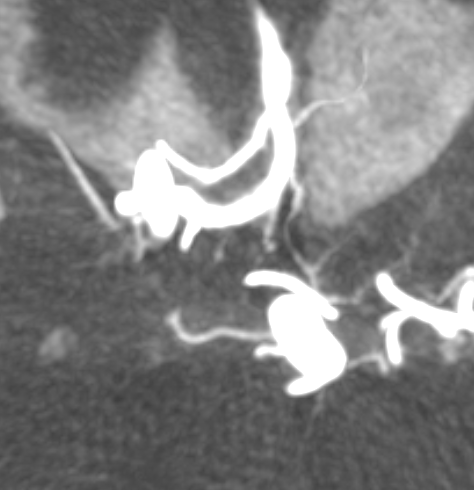

Capsular Arteries of McConnell

These are different from Superior Hypophyseals, but often come up together. This is because they were described by McConnell in a fantastic manuscript on arterial supply to the hypophysis. The anterior hypophysis is supplied by the aforementioned superior hypophyseals. Posterior by the inferior hypophyseals. The arteries of McConnell supply the dura and bone of the sella turcica. They are considered dural, and do not as a rule supply the hypophysis. Too small for even HR CBCT resolution, they are found in about 1/3 to 1/2 of surgical dissections. Origin is from the MEDIAL aspect of the horizontal cavernous segment (opposite side of ILT). Courses medially towards the bottom of the sella. Below (arrows) is a particularly large one (because it feeds some posterior pituitary for some reason). Note beautiful anterior pituitary / stalk supply on bottom right image.

Without arrows: